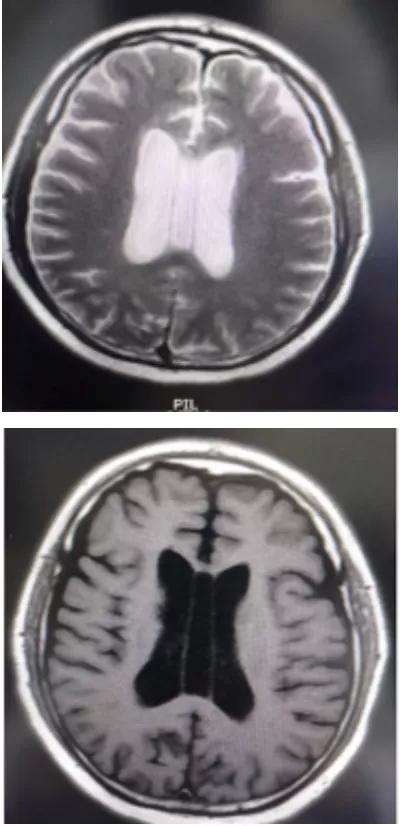

透明隔是两侧侧脑室中间的间隔,在胎儿四个月时原始透明隔内形成一个中缝,然后发展为分离的两个小叶,两小叶之间的间隙为透明隔间腔即CSP。腔的前上方为胼胝体,后下方为穹隆,侧壁即透明隔小叶。正常情况下,此腔将逐渐融合而消失。如到一定年龄尚未融合且由脑脊液填充,即形成CSP,它在透明隔发育畸形时更加膨大。CSP不属于脑室系统,因为它没有后者所具有的室管膜。但是经常与侧脑室或三脑室相通因为在气脑造影时可积满气体,那些不与脑室系统相通者.腔内的脑脊液通过透明隔膜过滤和隔膜静脉及毛细血管重吸收。

透明隔间腔是在颅内两层透明隔之间形成的腔隙,它的上界为胼胝体体部,前下方为胼胝体膝部及嘴部和前联合,底部和后方为穹窿。透明隔间腔被认为是人脑发育过程中的正常结构,通常在出生后的几个月内闭合,但该结构亦存在于少数成人中。但是,将透明隔间腔称为"第五脑室"是不正确的,因为它的内壁未衬有室管膜细胞,其内含有的液体也通常与脑室系统不同,因此透明隔间腔不具备脑室的组织结构特征。